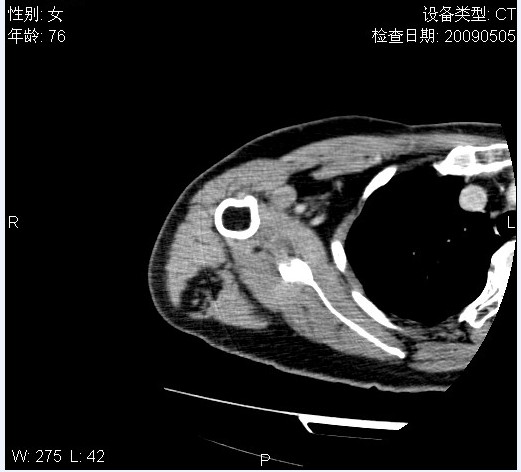

标题: CT19811:女,76岁,右上臂肿物1个月 [打印本页]

标题: CT19811:女,76岁,右上臂肿物1个月

使用了造影剂,可惜效果不太好

右肱骨上段软组织内见梭形低密度影,边界清楚,最长径约54mm.

病理结果:脂肪瘤。术中见肱骨骨膜受侵,有出血,量不详。

当时诊断意见:右肩三角肌内蔓状血管瘤(先天性动静脉瘘)。

本人对病理结果有个疑问:单纯的脂肪瘤内为什么有条状软组织影,那应该脂肪肉瘤才对啊?

该病例增强效果欠佳,由于经验欠缺,我们注射对比剂是由下肢足背静脉给药。注速2.0。虽然如此,但我们可以看到肿块内部条状软组织影是强化的,而且是连续的,并可见供血动脉是由腋动脉的其中一支即肩胛下动脉分出。从这些征象我们可以得出诊断:蔓状务血管瘤。

可病理偏偏为脂肪瘤,我怀疑取材有问题。因为蔓状血管瘤异常扩张的静脉外周是脂肪成分,它可以侵犯肌组织及骨骼。当取材于外周,那当然是脂肪瘤。此时我认为临床的最终诊断不应单从病理出发,应该综合考虑。